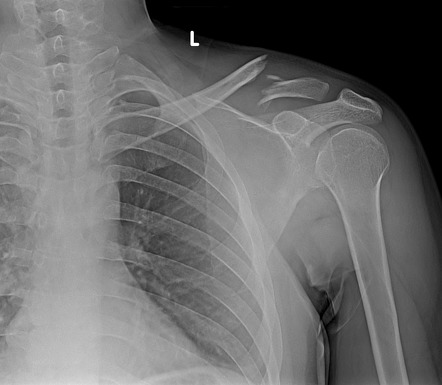

• Перелом ключицы

Перелом ключицы

2022-10-21

Переломы ключицы являются одними из самых частых переломов, на их долю приходится 3% всех переломов.Исторически его лечили консервативно, но результаты не всегда были положительными.Неоперативное лечение может привести к таким осложнениям, как боль, неправильное сращение и синдром грудной апертуры.Благодаря усовершенствованию методов хирургической фиксации многие хирурги решили использовать хирургическую фиксацию для лечения переломов ключицы со смещением.